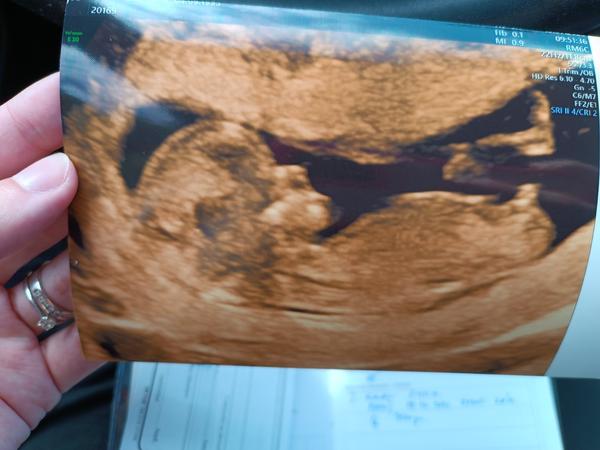

Bude to chlapeček podle hrbolku? Zkušenosti a tipy.

byla jsem na 1. screeningu a podle hrbolku to bude asi kluk, co?😄 Dr tipuje chlapečka. Za měsíc jdu na další kontrolu, tak jsem zvědavá, jestli už se to potvrdí nebo jestli se bude schovávat 😄

Chlapeček.

mám stejnou fotku,je to chlapeček.

Kluk celkem na jistotu :D

Normálně to nepoznám, ale tady bych taky řekla, že je to kluk 😀

@horhana esi je to hrbolek, tak kluk 100% 😁